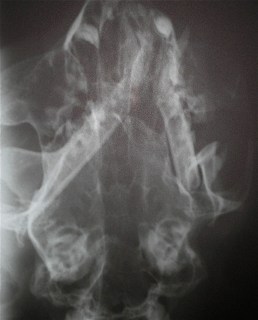

Κατάγματα κάτω γνάθου σε γάτα από Πέτρος Μπεάκος25/11/201007/12/2017Σχολιάστε Παραμόρφωση της κάτω γνάθου λόγω των καταγμάτων Λοξή ακτινογραφία κάτω γνάθου στην οποία φαίνονται τα κατάγματα της γενειακής σύμφυσης και του οπισθίου άκρου της γόμφιας μοίρας του σώματος Μετεγχειρητική ακτινογραφία Η σύγλειση των οδόντων μετεγχειρητικώς Κοινοποιήστε: Στείλε ένα σύνδεσμο σε έναν φίλο(Ανοίγει σε νέο παράθυρο) Email Εκτύπωση(Ανοίγει σε νέο παράθυρο) Εκτύπωση Mοιραστείτε στο Facebook(Ανοίγει σε νέο παράθυρο) Facebook Μοιραστείτε στο X(Ανοίγει σε νέο παράθυρο) Χ Μου αρέσει! Φόρτωση... Σχετικά